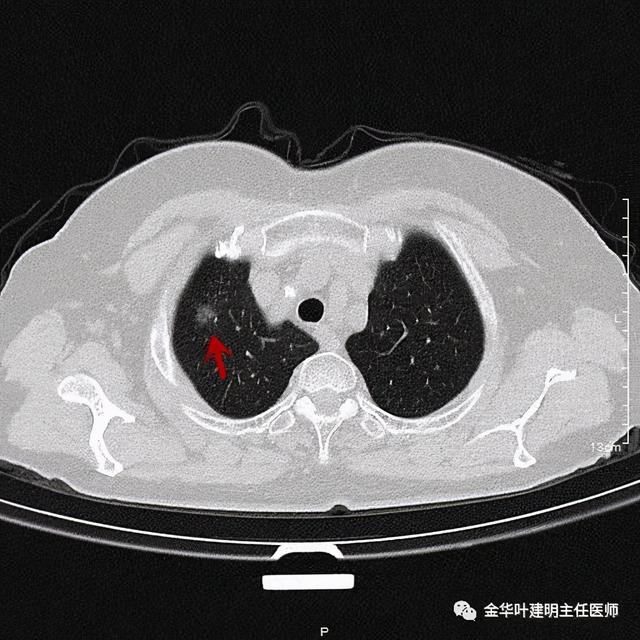

靶扫描更清楚显示瘤肺边界较清、分叶及密度不均杂乱 , 并有少许胸膜牵拉凹陷 , 当然考虑是肺癌 , 而且应该是浸润性腺癌了 。 其长径达2.5厘米!靶扫描还发现了平扫没被注意到的另一个病灶:

患者为女性 , 今年76岁 , 平时体质甚好 , 家务及地里劳动都胜任 , 头发仍乌黑(我自己倒有一半白发了) 。 肺功能与血气分析正常 。 CT检查图像如下:

可见右肺上叶混合磨玻璃结节 , 有明显分叶征 , 瘤肺边界虽然欠清楚 , 但轮廓比较清晰 。 看着也许会考虑炎性 , 但总觉得其比较僵硬 , 看去不舒服 。 这种病灶一是如果持续存在就极可能是肺癌 , 二是靶扫描显示更清晰的细节 , 如果瘤肺边界还是清楚的 , 也基本是肺癌 。 我们回顾发现其于2019年3月在我们医院做过CT平扫 , 当时报告如下: